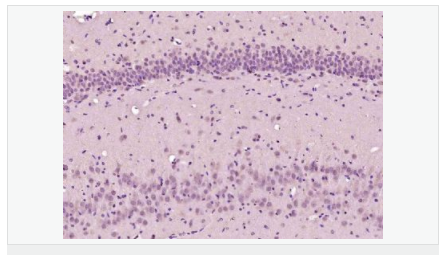

| 產品應用 | ELISA=1:5000-10000 IHC-P=1:100-500 IHC-F=1:100-500 ICC=1:100-500 IF=1:100-500 (石蠟切片需做抗原修復) not yet tested in other applications. optimal dilutions/concentrations should be determined by the end user. |